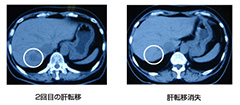

画像引用元:ニューシティ大崎クリニックHP(http://www.nco-clinic.jp/case/nyuugan.html) 乳がんから肝臓へ―【手術・抗がん剤・ホルモン療法効かず】乳がんから肝臓へ転移、手術などで一旦肝臓がんは消失したものの、再度肝臓への転移。抗がん剤とともに高活性NK細胞療法を併用し肝転移は消えその後の再発はなし。